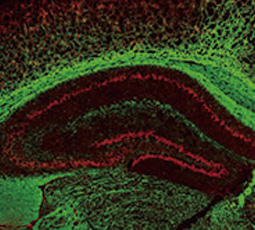

The main functions of oligodendrocytes are to provide metabolic support and neuronal axon myelination in the central nervous system (CNS), which is analogous to Schwann cells in the peripheral nervous system (PNS). Myelin sheaths generated by oligodendrocytes are able to facilitate fast neuronal action potential conduction along the axon. Loss of myelin sheaths due to oligodendrocyte dysfunction can lead to subsequent neuron degeneration and cause neuronal disorders such as multiple sclerosis.